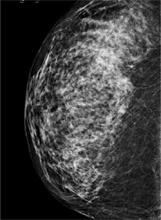

FIGURE

A digital mammogram showing normal but dense breast tissue